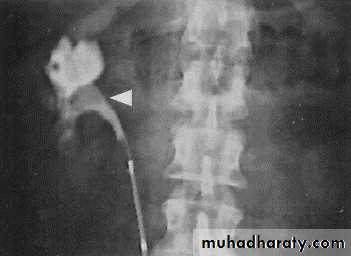

14- Retrocaval

16- Retrocaval